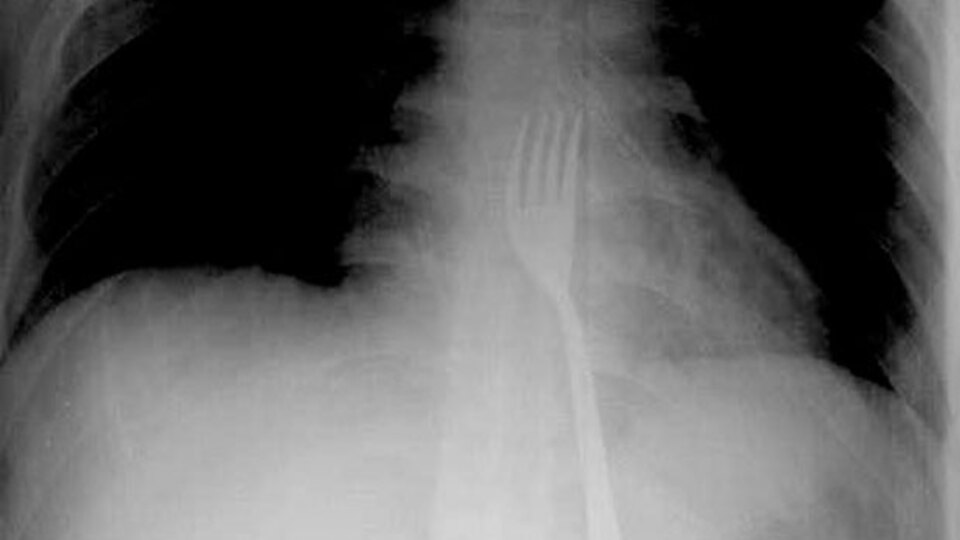

Konya'da zihinsel engelli 20 yaşındaki O.A.'nın yuttuğu 15 santimetrelik metal çatal, ameliyatla midesinden çıkarıldı.

Olay bir hafta önce meydana geldi. Zihinsel engelli O.A., ailesinin yanında bulunmadığı bir sırada yemek yediği çatalı ağzına soktu. Yemek borusunun sonuna kadar inen çatal midesinde kaldı. Durumu fark eden ailesi tarafından Necmettin Erbakan Üniversitesi Meram Tıp Fakültesi Hastanesi'ne kaldırılan O.A., acil olarak ameliyata alındı. 15 santimetrelik metal çatal yapılan operasyonla çıkarıldı.

Ameliyatı gerçekleştiren Necmettin Erbakan Üniversitesi Meram Tıp Fakültesi Hastanesi Genel Cerrahi Anabilim Dalı Öğretim Üyesi Prof. Dr. Mehmet Erikoğlu, hastanın acil servise başvurarak çatal yuttuğunu söylediğini belirtti. Yapılan muayene sonrası çatalın yemek borusunun sonuna kadar inip midede takıldığını tespit ettiklerini ifade eden Prof. Dr. Erikoğlu, mideden küçük bir kesi ile çatalı çıkarttıklarını anlattı.